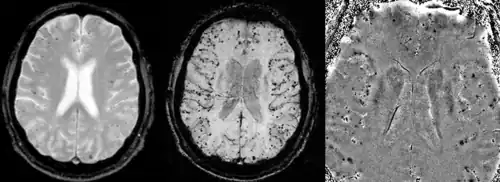

Gradient recalled echo (GRE) imaging is the conventional way to detect hemorrhage in CAA, however SWI is a much more sensitive technique that can reveal many micro-hemorrhages that are missed on GRE images.[7] A conventional gradient echo T2*-weighted image (left, TE=20 ms) shows some low-signal foci associated with CAA. On the other hand, an SWI image (center, with a resolution of 0.5 mm x 0.5 mm x 2.0 mm, projected over 8mm) shows many more associated low-signal foci. Phase images were used to enhance the effect of the local hemosiderin build-up. An example phase image (right) with yet higher resolution of 0.25 mm x 0.25 mm x 2.0 mm shows a clear ability to localize multiple CAA-associated foci.